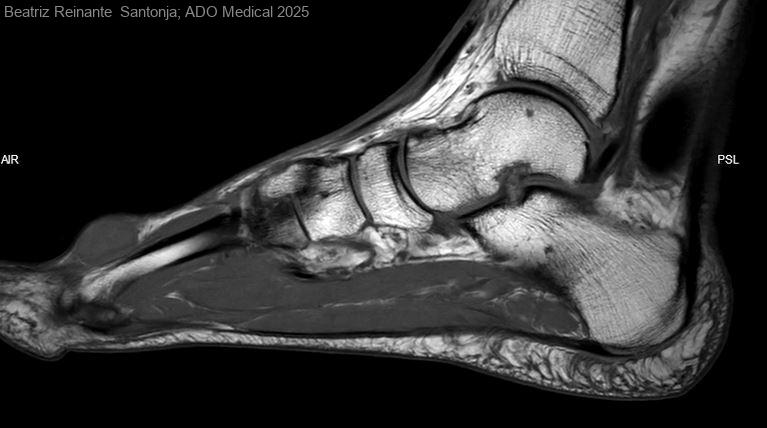

Varón de 60 años que acude a consultas de Truamatología, Unidad de Pie, presentando una tumoración de aproximadamente 0,5x0,5cm en el dorso del pie izquierdo. El diagnostico de sospecha inicial es de un ganglión. Para...